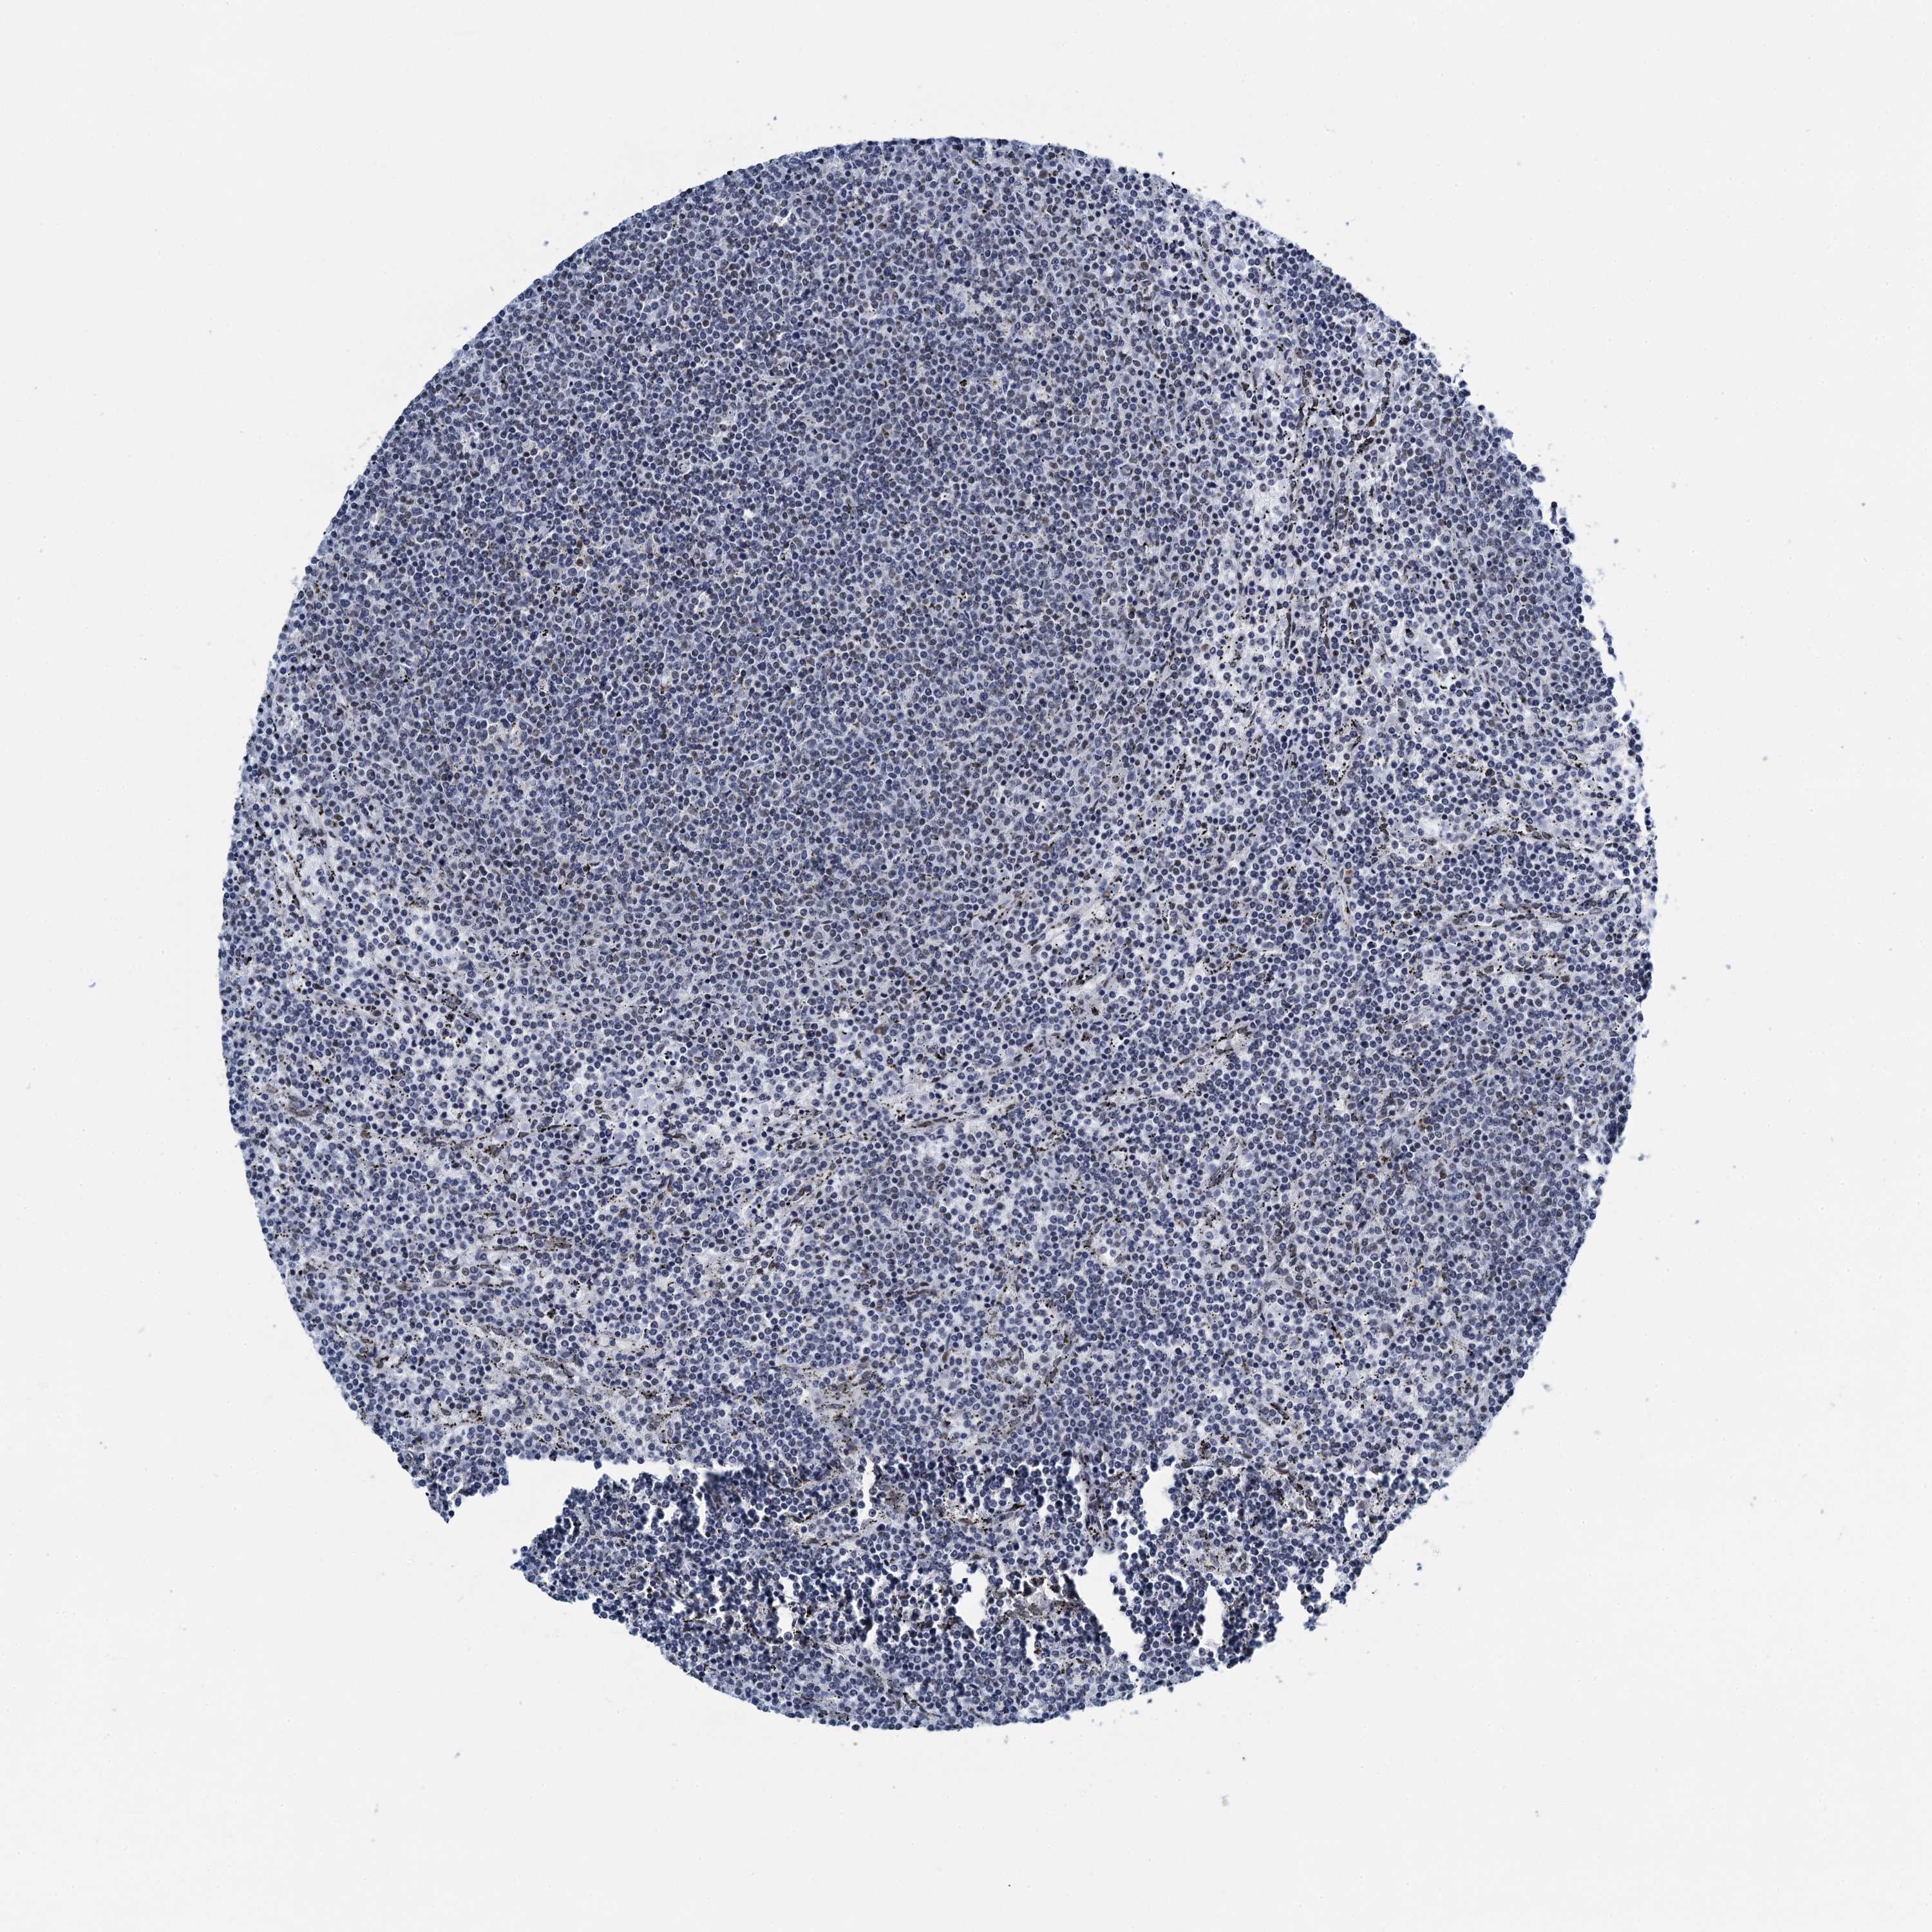

CANCER LYMPHOMA Show tissue menu

LYMPHOMA - Protein expressioni

A mouse-over function shows sample information and annotation data. Click on an image to view it in a full screen mode. Samples can be filtered based on level of antibody staining by selecting one or several of the following categories: high, medium, low and not detected. The assay and annotation is described here.

Antibody stainingi

Antibody staining in the annotated cell types in the current human tissue is reported as not detected, low, medium, or high, based on conventional immunohistochemistry profiling in selected tissues. This score is based on the combination of the staining intensity and fraction of stained cells.

Each image is clickable and will lead to virtual microscopy that enables deeper exploration of all samples and also displays staining intensity scores, fraction scores and subcellular localization as well as patient and tissue information for each sample.

Antibody HPA041632

Hodgkin's disease, NOS

Malignant lymphoma, non-Hodgkin's type, High grade

Malignant lymphoma, non-Hodgkin's type, Low grade